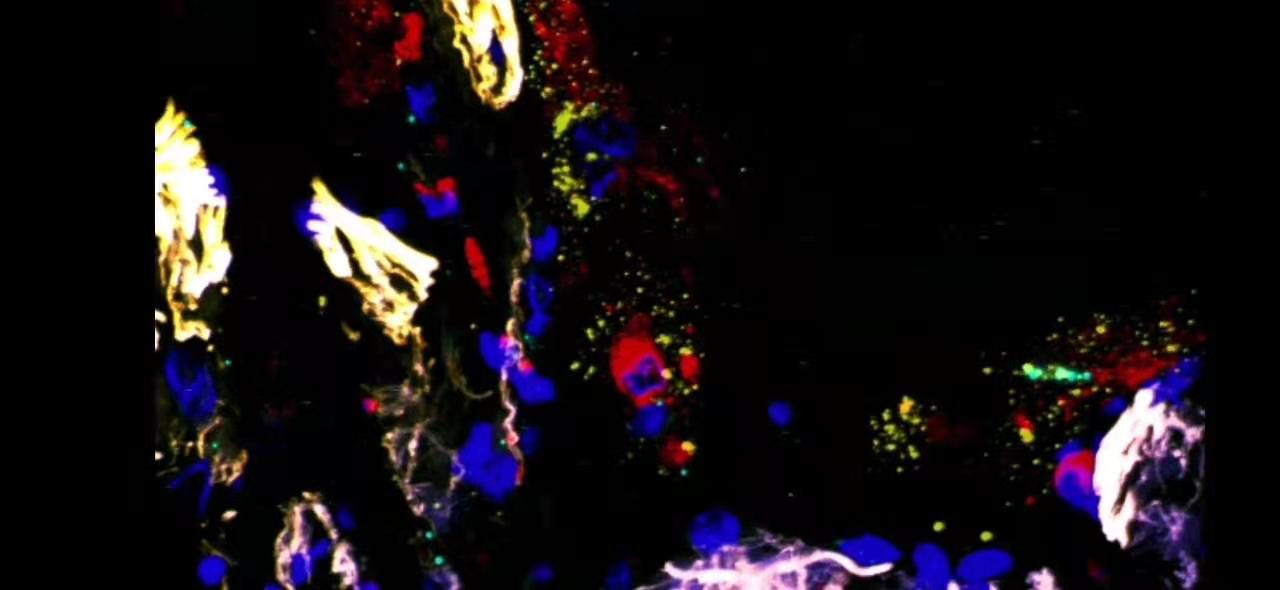

在CD206陽性肺泡巨噬細(xì)胞中檢測(cè)SARS-CoV-2陽性和陰性鏈轉(zhuǎn)錄產(chǎn)物。

結(jié)合免疫熒光顯微鏡檢查CD206(一種成熟的巨噬細(xì)胞(紅色))和smFISH(RNAscope)用于SARS-CoV-2陽性(黃色)和陰性(青色)轉(zhuǎn)錄產(chǎn)物。